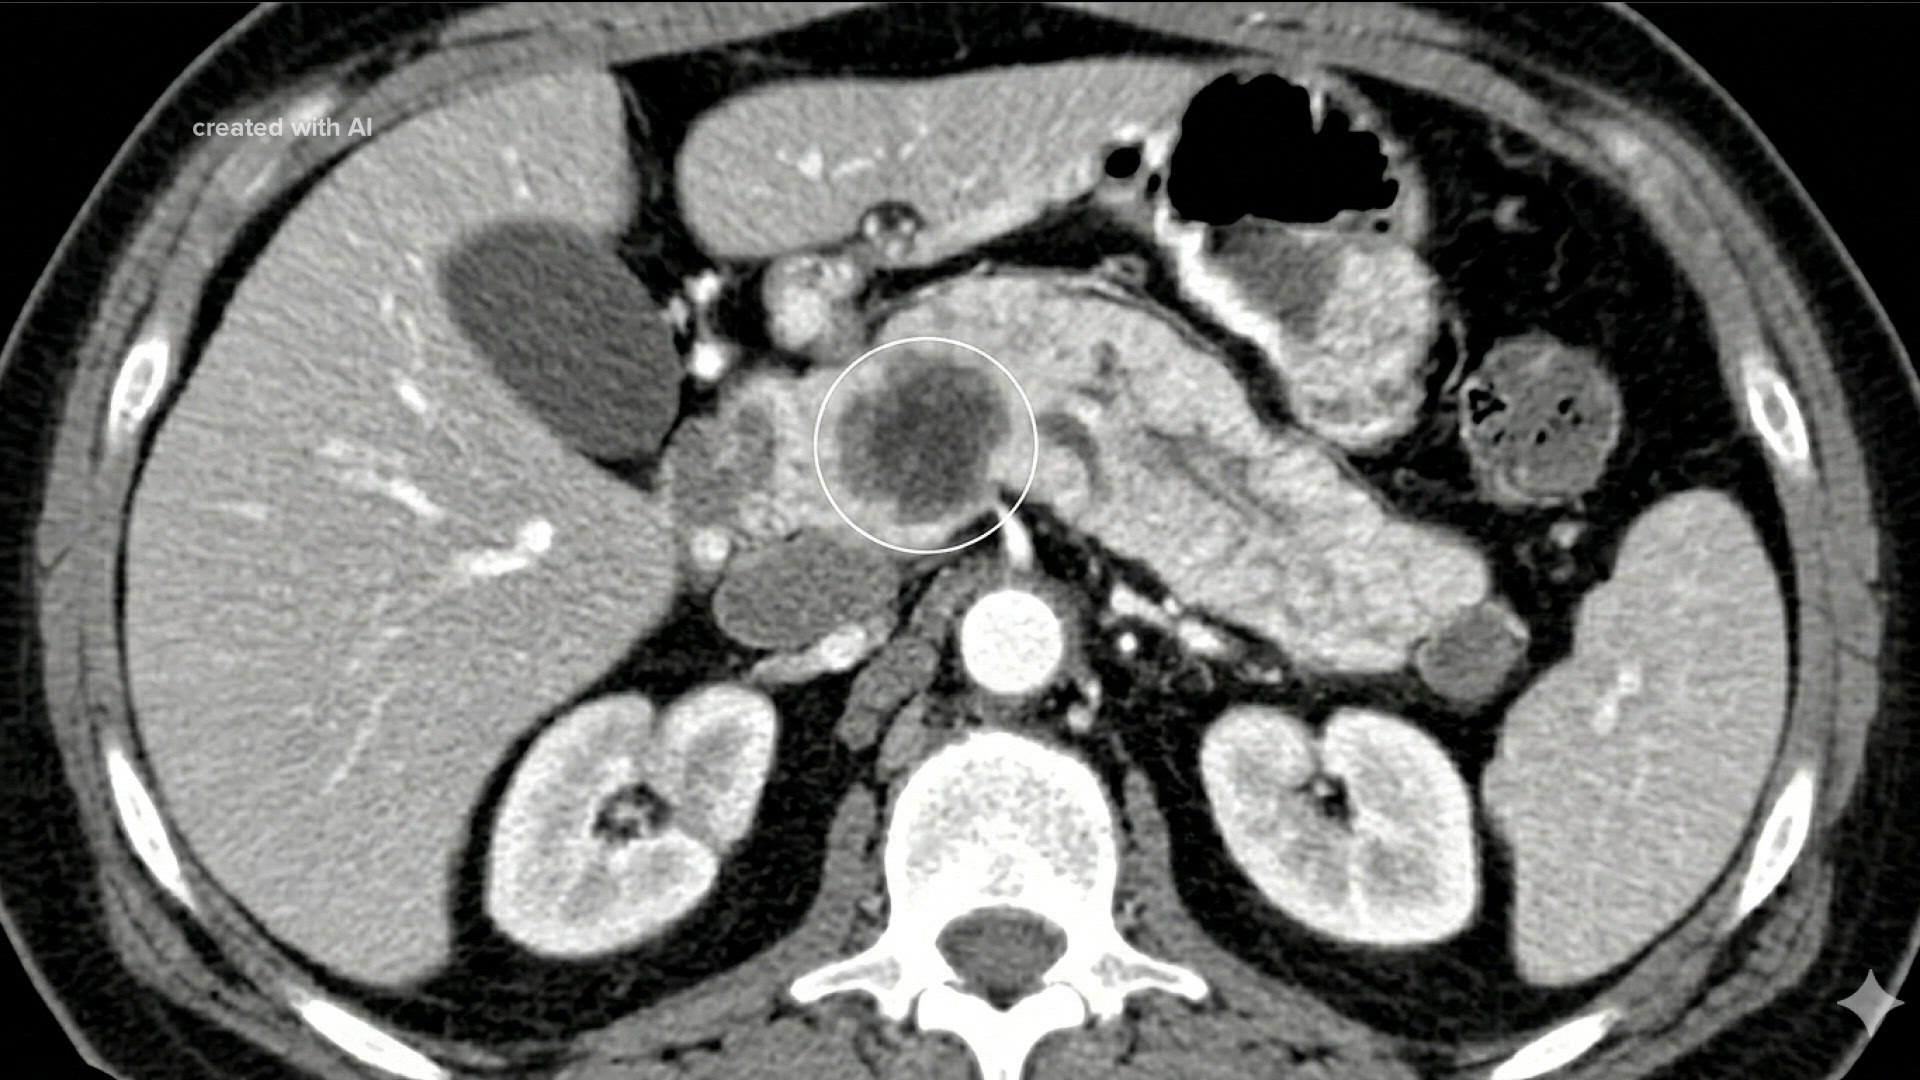

Selon The Straits Times, the system, called Redmod, analyses patterns in CT images that are not visible to the human eye. The Straits Times indique que ROCHESTER, Minnesota - An artificial intelligence (AI) system can spot pancreatic cancer long before it shows up on scans, raising the prospect of catching one of the deadliest tumours early enough to successfully treat it, a study found. D'après The Straits Times, Pancreatic cancer is rarely detected early because tumours typically do not cause symptoms and often are not visible on imaging until the disease is advanced. Comme le souligne The Straits Times, the findings point to a potential shift in how pancreatic cancer is diagnosed – from reacting to symptoms late in the disease to identifying patients at risk years earlier.

“Modelling studies indicate that increasing the proportion of localised pancreatic ductal carcinomas from 10 per cent to 50 per cent would more than double survival rates, thereby underscoring that the timing of diagnosis is the single most critical determinant of survival outcomes.” (The Straits Times) D'après The Straits Times, the model, developed by researchers at Mayo Clinic and collaborators, identified subtle changes in routine computerised tomography scans, or CT scans, an average of about 475 days before patients were diagnosed, according to the study, published on April 28 in the journal Gut. Comme le souligne The Straits Times, more than 85 per cent of cases are found at a stage where treatment is largely limited to easing symptoms, helping explain why the five-year survival rate is about 10 per cent globally. Selon The Straits Times, it correctly identified 73 per cent of cases, compared with about 39 per cent for doctors reviewing the same images.

It was trained and tested on scans from more than 1,400 people, including 219 patients whose earlier scans had been read as normal but who later developed pancreatic cancer.

• The study, which was published in the medical journal Gut, reviewed approximately 2,000 CT scans, including those from patients later diagnosed with pancreatic cancer.